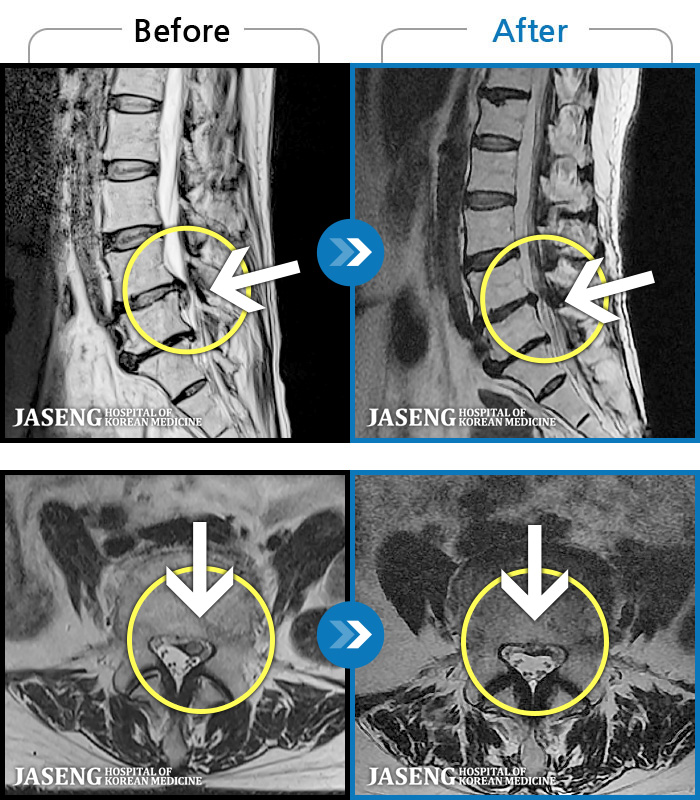

푸쉬업을 여러 번 반복한 뒤 극심한 하요부 통증 및 우측 하지부 저림

2024.03.21 ~ 2024.09.23